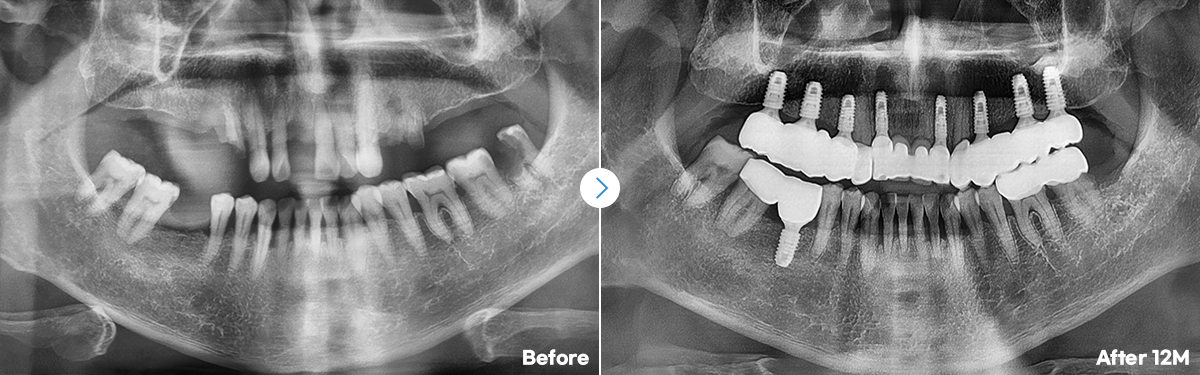

임플란트 개수가 많아도,

안정적이고 정확한 식립!

오차없이 초정밀 식립 3D 데이터로 철저한 수술계획네비게이션 임플란트